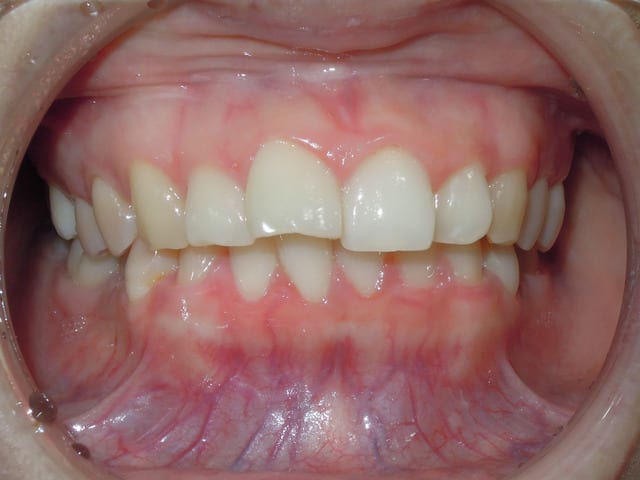

Quand soudain ..

Suite a un problème d'emplois du temps la patient n'a pas pus venir pendant deux mois, a sont retour nous avons la situation suivant .

- open bite

- over jet

La question est donc เกิดอะไรขึ้น